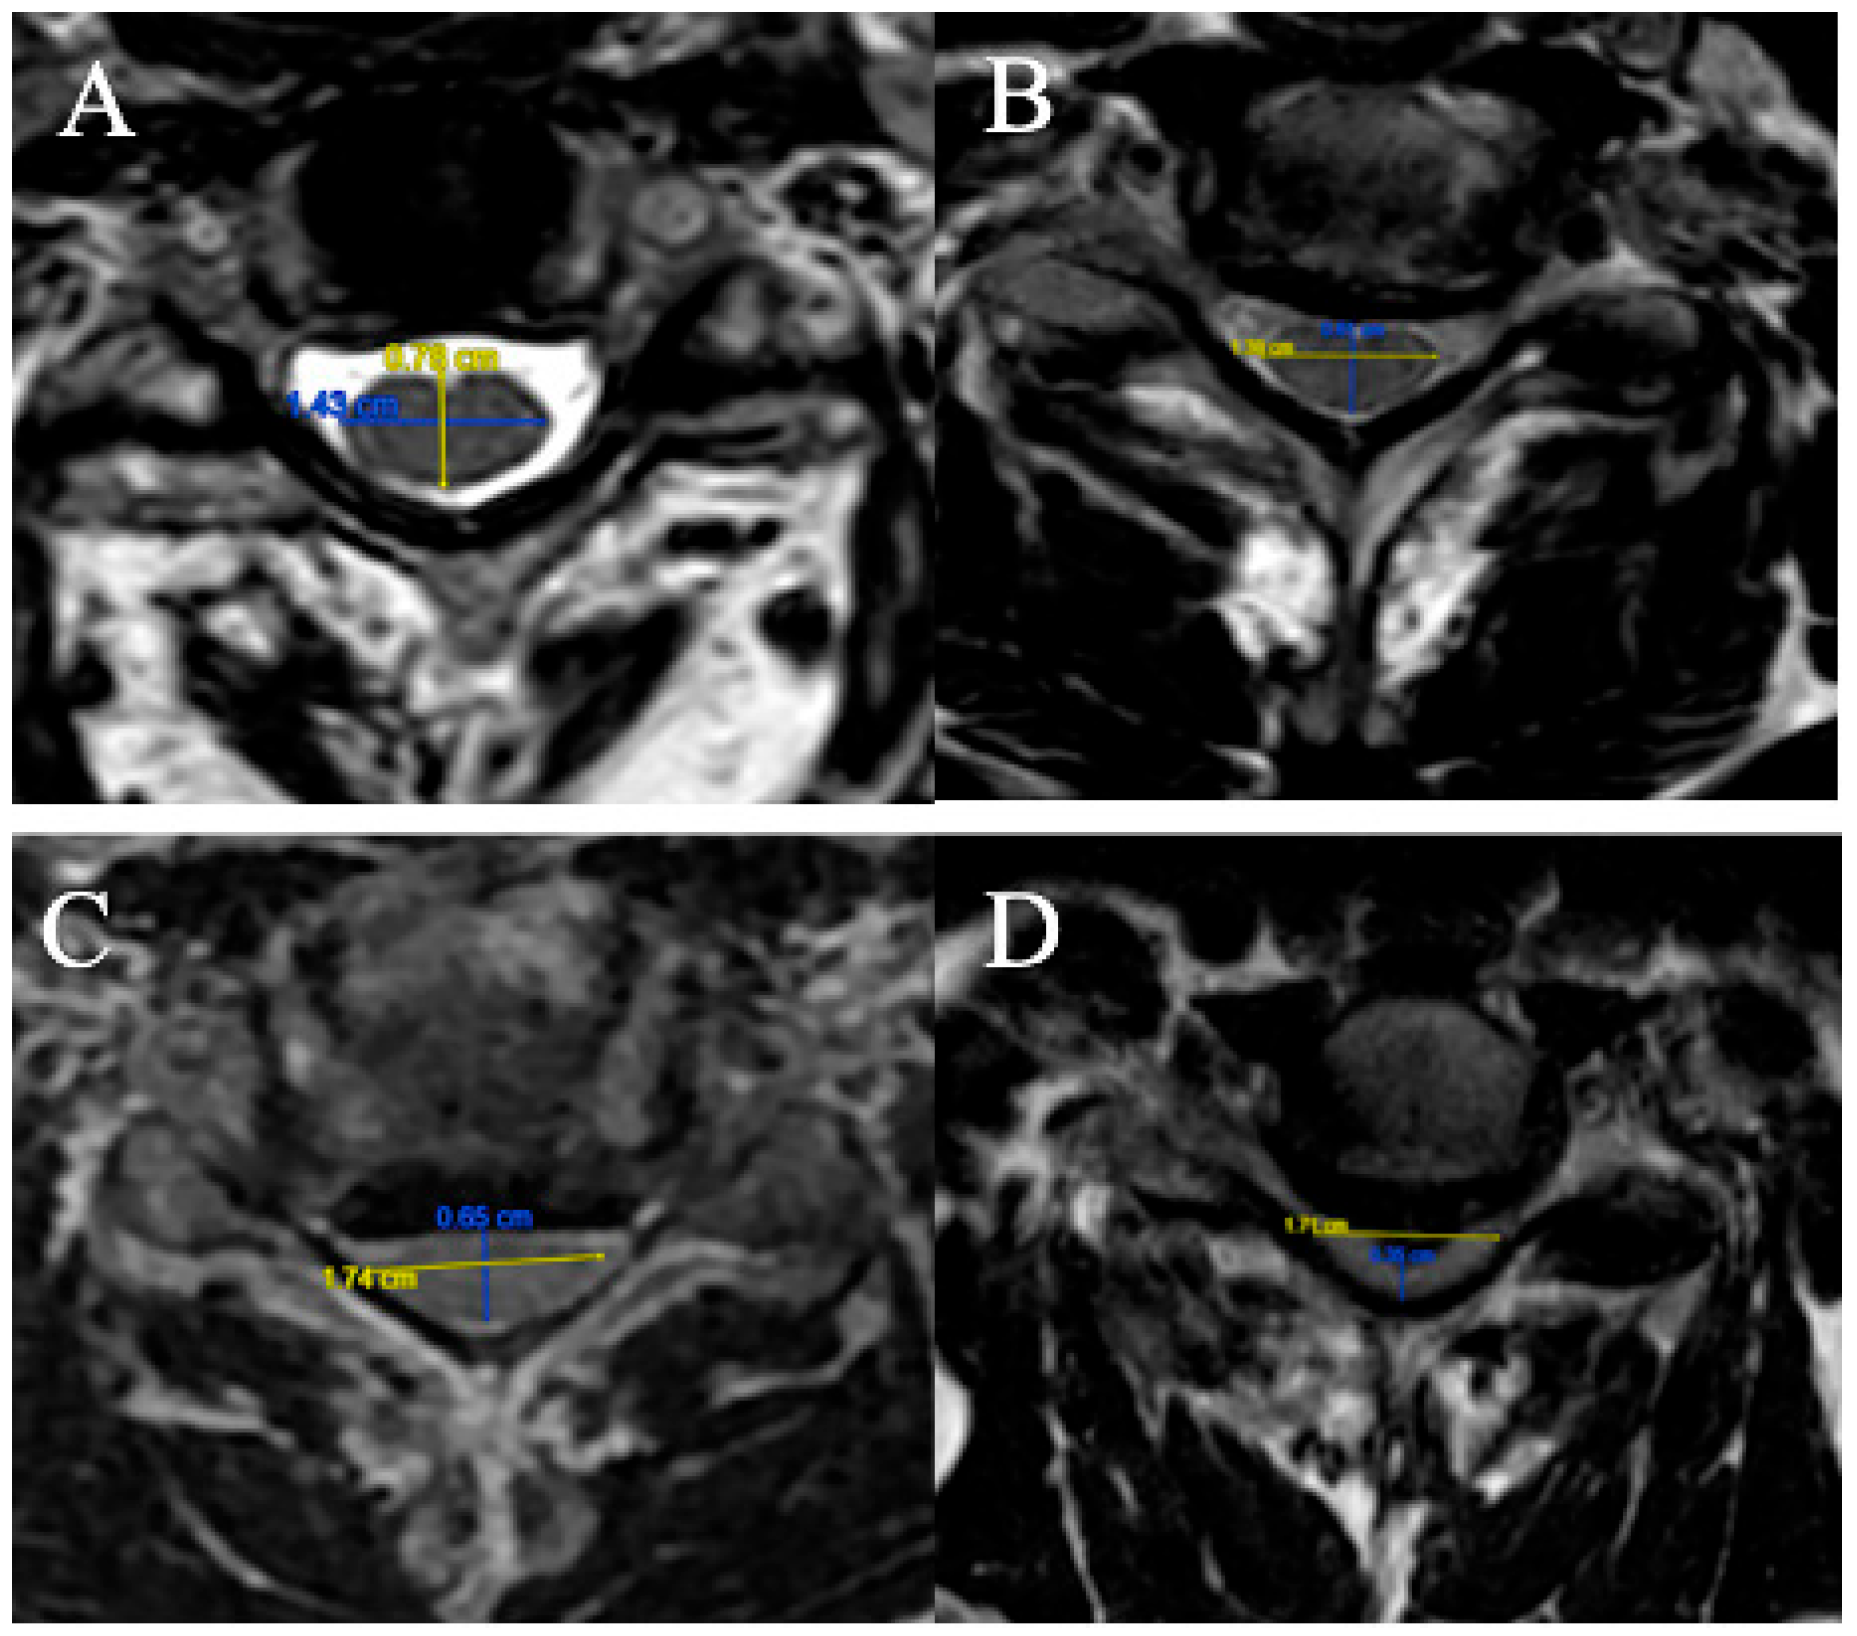

2.3.4. Torg–Pavlov Ratio

Three grades were selected (based on T2-weighted sequence on median sagittal sections at the middle vertebral level overlying the compression) (Figure 4). The Torg–Pavlov ratio is calculated using the sagittal canal-to-vertebral body ratio:

(A) TPR ≥ 0.8;

(B) 0.6 ≤ TPR < 0.8;

(C) TPR < 0.6.

Figure 4. Example of measurement of the TPR. (A) TPR = 0.85; (B) TPR = 0.75; (C) TPR = 0.59.